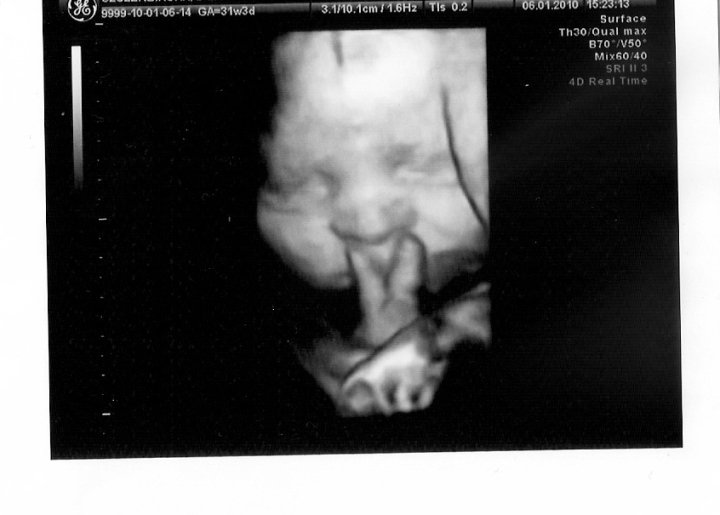

To zdjęcie jest wyrwane z kontekstu i bez niego hmm… faktycznie może sprawiać wrażenie “nie na miejscu”. Ale kontekst jest taki, że na usg ciążowym lekarz “złapał” Emilkę z palcami przy nosie i nawet udało mu się zrobić takie zdjęcie: https://www.podrozezesmakiem.com/wp-content/uploads/2016/08/25178_1407795317511_3014086_n.jpg. Ten gest bardzo poruszył i jego i nas, i wszystkie pielęgniarki, które przybiegły pooglądać dziecko na ekranie. Potem, po przyjściu na świat, Emilka bardzo często przykładała palce do nosa w tym geście – my uważaliśmy, że to V, jak Victoria ;) Szczególnie kiedy była zmęczona wyciszała się w ten sposób. Nie było to dłubanie w nosie, po prostu robiła z palców V, przykładała je do nosa i tak długo je tam trzymała póki nie zasnęła. Wiedzieliśmy, że to nawyk z życia płodowego.

A kiedy powstawał ten blog, nie zaglądał tu pies z kulawa nogą, więc to zdjęcie było przeznaczone dla rodziny i przyjaciół, którzy doskonale rozumieli jego kontekst.

Mam nadzieję, że choć trochę wytłumaczyłam sens tego ujęcia. Nie zwykłam robić zdjęć dzieciom, ani nikomu, w sytuacjach wstydliwych ;)

Serdecznie pozdrawiam! :)